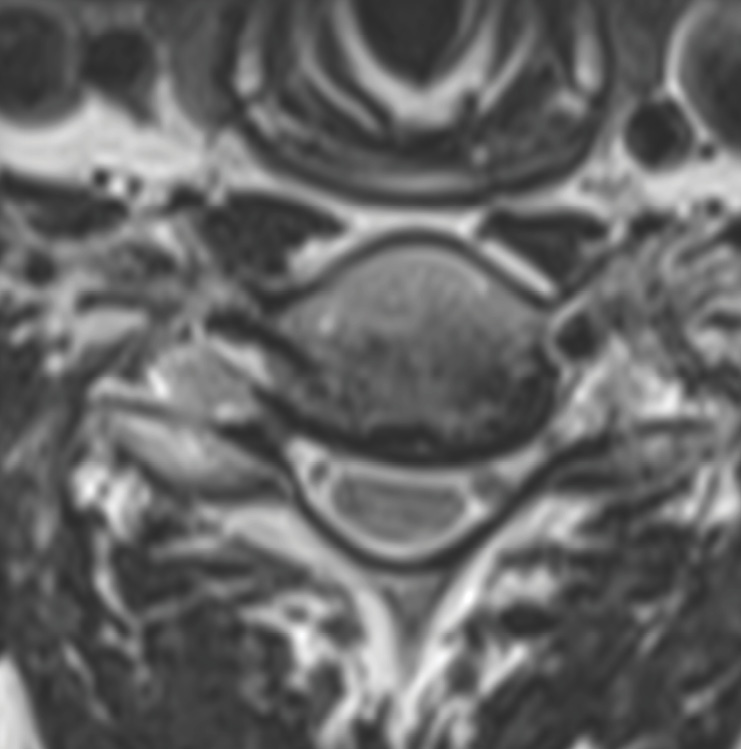

Pre-op MRI demonstrates partial disc height collapse and foraminal stenosis at C5-6 and C6-7.